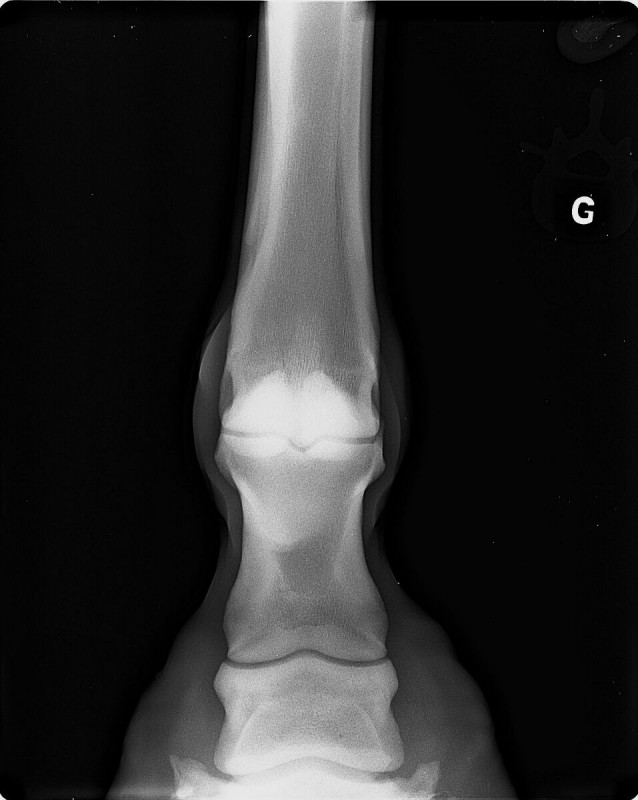

Radios que voici (on "voit" la boule, à gauche sur la deuxième radio et à droite sur la troisième) :